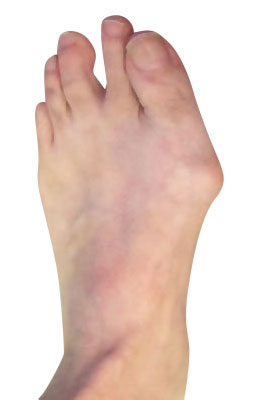

Before

Minimally Invasive Bunion Surgery before

After

Minimally Invasive Bunion Surgery after

Minimally Invasive Bunion Surgery featuring the miniBunon™ System and Tailors Bunionectomy

Melissa is a 32-year-old businesswoman who could not be off her foot post-surgery, yet she had a severely painful bunion. We performed our miniBunon™ System (our trademarked minimally invasive bunion surgery) and had a dramatic correction with no downtime. Melissa continued to work after her bunion surgery and was back in shoes and full activity at 5 weeks. Melissa could not believe the results of her Bunionectomy resulting in no bony bump, no scar and amazing motion. “After” picture taken immediately following surgery. Note the bunion and bunionette (Tailor’s bunion) in the before picture.